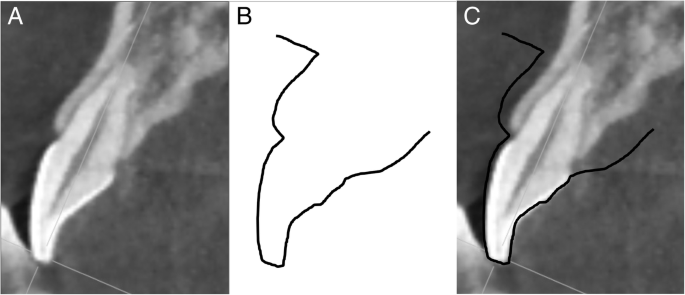

After scanning each patient’s cast with a digital intraoral scanner (Trios Pod, 3shape dental systems, Copenhagen, Denmark), each anterior tooth in the virtual model was sectioned via a line connecting the midpoint of the incisal edge and the midpoint of the cementoenamel junction (CEJ) (Fig. 1). Tooth section images were acquired for 4 upper and lower anterior teeth. This type of cast scanning is different from intraoral scanning in that patient cast impressions were scanned using an intraoral scanner.

Each CBCT image was acquired by sectioning via a line connecting the midpoint of the incisal edge and the root apex using software (OnDemand 3D, Cybermed Co., Seoul, Korea) for each of 4 upper and lower anterior teeth (Fig. 2).

Superimposition